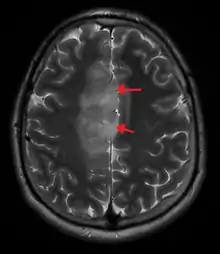

A oligoastrocytoma on MRI

An X-ray computed tomography (CT) or magnetic resonance imaging (MRI) scan is necessary to characterize the anatomy of this tumor as to size, location, and its heter/homogeneity. However, final diagnosis of this tumor, like most tumors, relies on histopathologic examination (biopsy examination).[3]